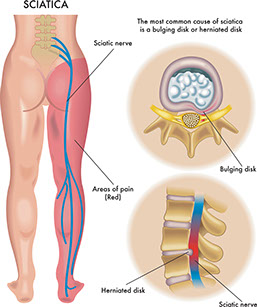

Sciatica

Signs & Symptoms

Sharp pain from the buttocks down the leg. Numbness and tingling in the leg.